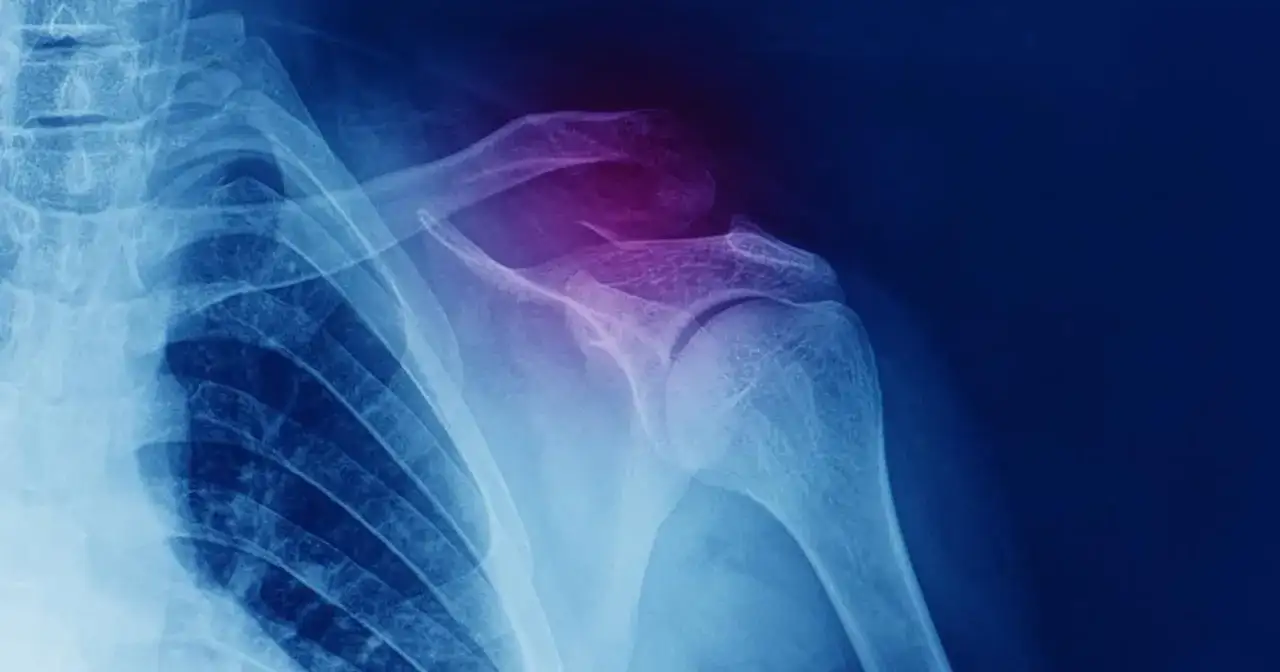

Złamanie obojczyka to uraz, który może wywołać spory niepokój i wiele pytań. Jak długo potrwa powrót do zdrowia? Czy moje złamanie będzie goiło się inaczej niż u innych? Jak mogę sobie pomóc w tym trudnym czasie? W tym kompleksowym przewodniku znajdziesz odpowiedzi na te i inne kluczowe pytania dotyczące procesu gojenia złamanego obojczyka. Przygotowałam dla Ciebie praktyczne informacje, które pomogą Ci zrozumieć etapy rekonwalescencji, czynniki wpływające na tempo leczenia oraz jak skutecznie wrócić do pełnej sprawności. Wiedza to pierwszy krok do spokoju i efektywnego powrotu do zdrowia.

Proces leczenia złamanego obojczyka można podzielić na dwa główne etapy. Pierwszy to zrost kostny, czyli moment, w którym kość zaczyna się łączyć. Zazwyczaj trwa on od 4 do 8 tygodni. To kluczowy okres, w którym musimy dać kości czas na regenerację. Jednak sam zrost kostny to nie koniec drogi do pełnej sprawności. Drugi etap to rekonwalescencja, która obejmuje odzyskanie pełnego zakresu ruchu w stawie barkowym i siły mięśniowej. Ten etap może potrwać znacznie dłużej, od 3 do nawet 6 miesięcy. Pamiętaj, że są to wartości uśrednione i każdy przypadek jest indywidualny. U dzieci proces ten przebiega zazwyczaj znacznie szybciej zrost może nastąpić już po 3-4 tygodniach, co jest związane z ich dynamicznym metabolizmem i lepszym ukrwieniem tkanek.

Po urazie, pierwszym krokiem jest zwykle unieruchomienie złamanego obojczyka, najczęściej za pomocą ortezy typu ósemka lub temblaka. Ma to na celu stabilizację odłamów kostnych i zapewnienie im optymalnych warunków do zrostu. W tym okresie kluczowe jest oszczędzanie kończyny i unikanie ruchów, które mogłyby pogorszyć stan. Gdy lekarz lub fizjoterapeuta oceni, że zrost kostny postępuje prawidłowo, rozpoczyna się pierwszy etap rehabilitacji. Często obejmuje on bardzo delikatne ćwiczenia, takie jak ruchy palców, nadgarstka czy łokcia, aby zapobiec sztywności i utrzymać krążenie. Dopiero po uzyskaniu stabilnego zrostu można przejść do właściwej rehabilitacji, która koncentruje się na stopniowym odzyskiwaniu pełnego zakresu ruchu w stawie barkowym i wzmacnianiu osłabionych mięśni. To właśnie ten etap jest kluczowy dla powrotu do pełnej funkcjonalności i aktywności sprzed urazu.